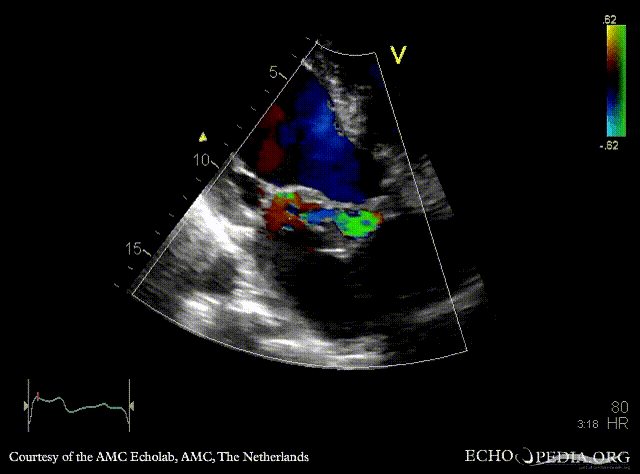

E00846.gif E00847.gif

PSAX: abscess of aortic valve prosthesis A4CH with Color Doppler: flow from abscess into the left atrium, severe mitral regurgitation